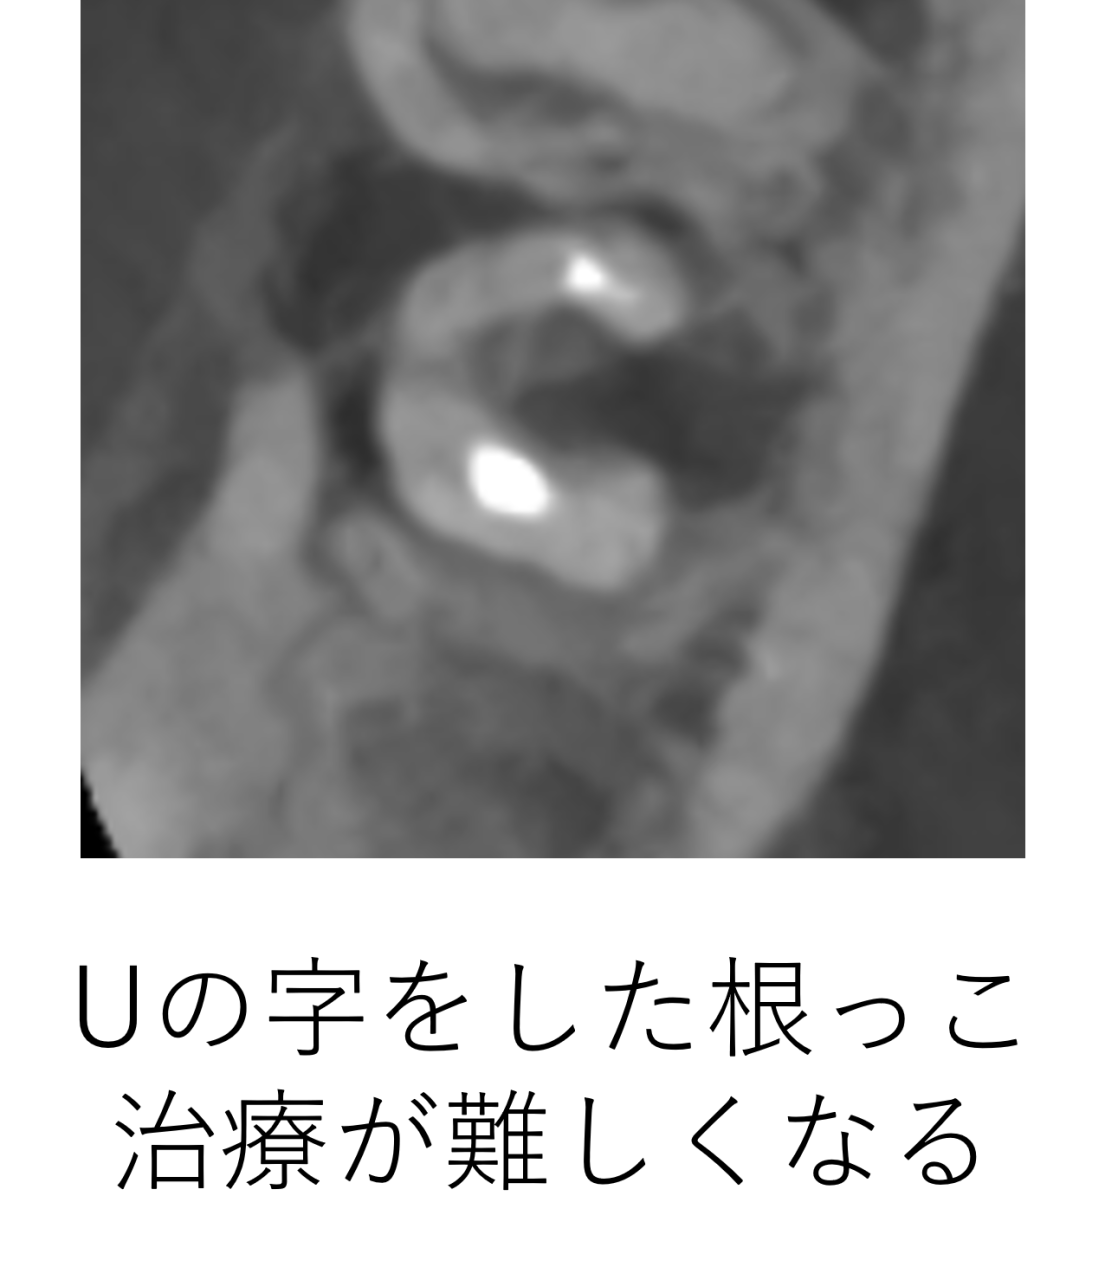

上からの断面図を見ると、この歯はUの字の形をしています。この場合神経の形がとても複雑になるので、治療は難しくなります。

この形の場合、このUの真ん中のところにも神経があることがほとんどなので、おそらく神経の大元の部分も取り残されている事が予想されました。